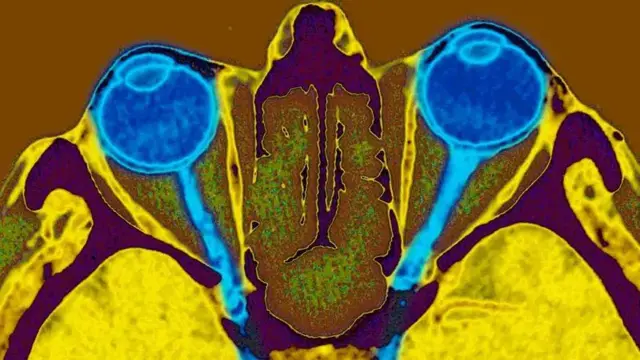

ब्रिटिश पत्रिका 'ओप्थैमोलॉजी' में प्रकाशित एक अध्ययन के मुताबिक़, मेथेनॉल की थोड़ी मात्रा भी नर्वस सिस्टम यानी तंत्रिका तंत्र को बुरी तरह प्रभावित कर सकती है, इससे आँखों की रोशनी ख़त्म हो सकती है और इसे वापस हासिल करना भी संभव नहीं होता है.

इसमें कहा गया है कि अगर कोई इंसान अवैध शराब की वजह से अपनी आंखों की रोशनी खो दे, तो चिकित्सा की सबसे आधुनिक तकनीक भी आंखों को दोबारा ठीक करने में विफल हो सकती है.

विकास सोडीवाला कहते हैं, “मेथेनॉल, इंसान की आँखों की तंत्रिकाओं को प्रभावित कर सकता है और कुछ मामलों में वो अंधे भी हो सकते हैं.”